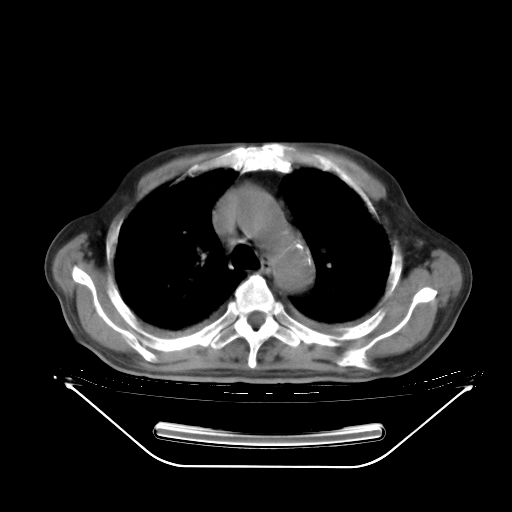

胸腹部CT,诊断意见:左上肺叶钙化灶、左侧胸膜局限性增厚并钙化、胆囊炎。描述部分肺组织呈磨玻璃样改变。